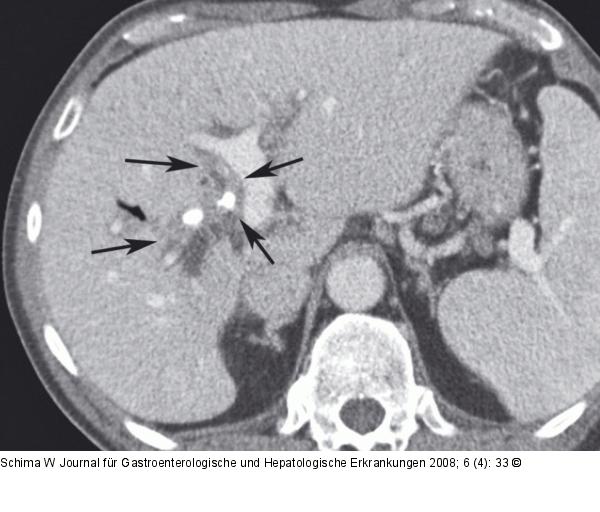

Abbildung 1a: Hypodenser Tumor Die MDCT zeigt einen hypodensen Tumor am Hilus, der entlang der Pfortaderbifurkation wächst (Pfeile) und zu einer Cholangiektasie führt. Zwei Gallengangstents in situ. |

Die MDCT zeigt einen hypodensen Tumor am Hilus, der entlang der Pfortaderbifurkation wächst (Pfeile) und zu einer Cholangiektasie führt. Zwei Gallengangstents in situ. |